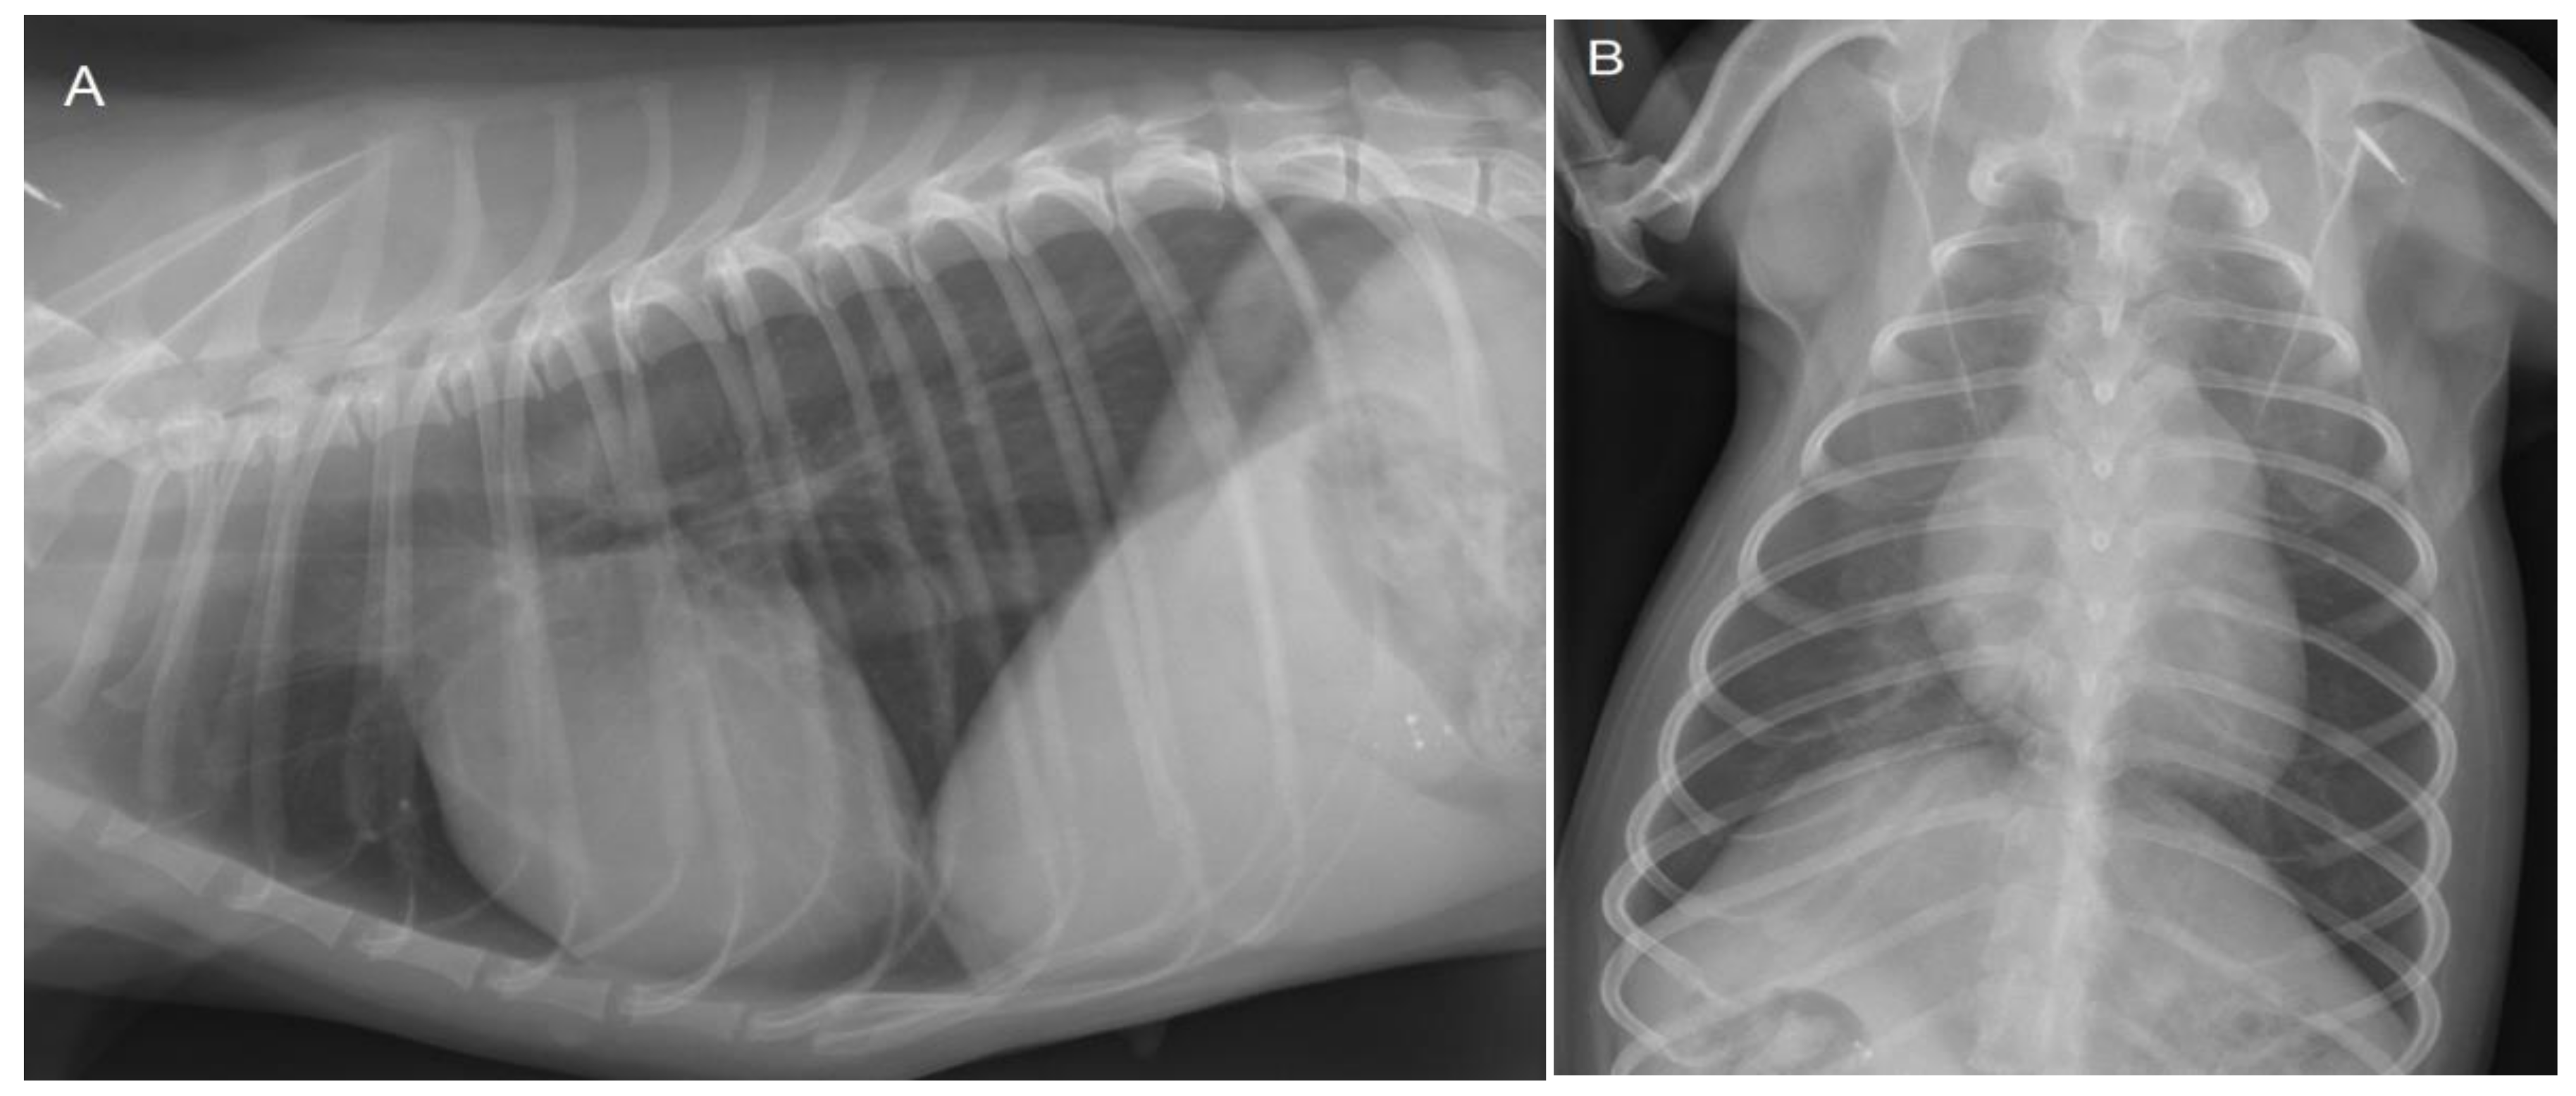

Because of the history of respiratory distress, thoracic radiographs were made, which revealed no abnormalities (Figure 2).

Figure 2. Lateral (A) and dorso-ventral (B) thoracic radiographs show no abnormalities at 3 years of age. The cardiac silhouette has a normal size and shape in both projections. The vertebral heart scale (VHS) is 10.5, which is within the breed-specific reference range for chihuahuas (8.9–11.0) [14]. There are no changes in the pulmonary parenchyma and pulmonary vasculature visible.